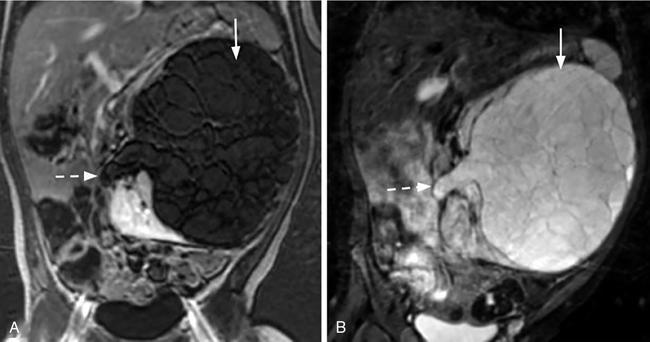

Naren Hemachandran, Devasenathipathy Kandasamy, Geetika Khanna Renal neoplasms are rare in children, accounting for less than 10% of childhood cancers. Nonneoplastic conditions like hydronephrosis, hypertrophied column of Bertin, foetal lobulations, calyceal diverticulum, simple renal cyst and infective causes like acute pyelonephritis, renal abscess can present as a renal mass clinically or on imaging. These nonneoplastic conditions are more common than true neoplasms in the early infantile period and radiologists should be aware of these conditions to avoid misdiagnosing them as neoplasms. In this chapter, we describe a clinic-radiological algorithmic approach as well as review the common paediatric renal neoplasms. Renal neoplasms can present as abdominal distension, mass palpable per abdomen (commonly detected by parents while bathing a child), flank pain, haematuria or rarely with other atypical symptoms. Imaging plays an important role in the detection, characterization, preoperative staging, image guided sampling, treatment planning and posttreatment follow-up or surveillance. Ultrasonography is the initial modality for detection as well as characterizing a mass as solid or cystic. This differentiation plays an important role in characterizing renal masses in children as further elaborated in this chapter. Computed Tomography (CT) is the preferred modality for further evaluation due to high spatial and temporal resolution and short scan times. In addition, CT allows for simultaneous evaluation for lung metastasis, a critical part of staging. Due to the need of sedation or general anaesthesia because of the longer acquisition time, Magnetic Resonance Imaging (MRI) is primarily used as a problem-solving tool and for evaluation of bilateral renal neoplasms. The characterization of renal masses in children may not always be possible by imaging due to significant overlap in the imaging and clinical features. In this chapter, we propose a radiological algorithm for the characterization of various renal masses in children. This is based on the primary nature of the mass and they are classified into predominantly fat containing, predominantly cystic and predominantly solid groups (Fig. 10.9.1). Predominantly solid masses are further subclassified based on the age at presentation. Various neoplasms have been categorized into these groups based on the most typical findings. This radiological algorithm is not absolute but intends to provide a practical approach to narrow down the differential diagnosis in a child with a renal mass. Angiomyolipoma is the most common fat-containing renal neoplasm in children. Other lesions like renal cell carcinoma, Wilms’ tumour also can show fat within. However, in such cases, fat component is seen along with other solid/cystic components and these do not present as predominantly fat containing and hence are described elsewhere. Angiomyolipomas are benign neoplasms and are composed of varying amounts of dysmorphic blood vessels, smooth muscle and fatty elements. In the adult population, the majority of them are sporadic, while the remaining 20% are seen in association with tuberous sclerosis. However, in children, the majority of the detected lesions are seen in association with tuberous sclerosis. The presentation varies with the size of the lesion. Small angiomyolipomas are typically detected during screening/annual surveillance of children with tuberous sclerosis. Those more than 4 cm are more likely to undergo spontaneous haemorrhage and present with pain, haematuria or rarely with life-threatening retroperitoneal or subcapsular haemorrhage. Although they are benign neoplasms, rarely they can show extension into the renal vein and subsequently into the inferior vena cava. On imaging, identification of a predominantly fat-containing mass enables us to confidently diagnose an angiomyolipoma (Fig. 10.9.2). However, there can be significant variation in the amount of fat within the lesion and some authors classify them into fat rich and fat poor angiomyolipomas. The fat can be either macroscopic fat or microscopic fat. The imaging features vary depending on the fat content. On ultrasonography, they are usually hyperechoic. The degree of heterogeneity of the lesion and the vascularity increases with increase in size of the lesion. Intratumoural prominent vessels, vascular lakes and pseudoaneurysms are well demonstrated on colour Doppler. CT is very helpful for the detection of the macroscopic fat even in smaller lesions. MRI helps in the demonstration of microscopic fat using chemical shift imaging, in which microscopic fat shows typical drop in signal intensity in opposed-phase images compared to in-phase images. Dixon technique is also very well suited for detection of small fat-containing angiomyolipomas, as the small foci of fat are very conspicuous on fat only images. The most common lesions that show predominant cystic areas on imaging are multilocular cystic nephroma, cystic partially differentiated nephroblastoma (CPDN)/cystic Wilms’ tumour. Previously these three tumours were considered to be along the same continuum with increasing blastemal components in CPDN compared to cystic nephroma, though recent studies have shown that these are distinct clinical/pathological entities. Multilocular cystic nephroma is a benign neoplasm more commonly seen in young boys. On sonography it appears as multiloculated cystic lesions with multiple thin septae within. The walls of the cyst and the septae show smooth thin enhancement on postcontrast imaging with no nodular or solid enhancing areas. The microcystic type can artifactually appear solid on imaging. These tumours typically present as Bosniak 3, and less commonly as Bosniak 2 renal cysts. Herniation into the collecting system is a characteristic finding, although it is not always seen (Fig. 10.9.3). Recent studies have shown a strong association of multilocular cystic nephroma with DICER-1 mutation. The lungs should be evaluated in these children for associated cystic lesions which can represent pleuropulmonary blastomas. The presence of solid enhancing component within a predominantly cystic lesion or nodular enhancement along the septae of a cystic lesion point towards a diagnosis of cystic Wilms’ tumour. Clinical, demographic features and the response to chemotherapeutic agents are similar to that of Wilms’ tumour, which is considered in detail in the next section. Most of the renal neoplasms in children are predominantly solid with significant overlap of imaging and clinical features. There are some typical features which are however, not seen always. We have further divided the predominantly solid masses based on the mean age of presentation of the lesions. This approach is not infallible, due to the wide range of the age of presentation of these lesions, and only aims to provide a practical working algorithm. Many times, even after the best of the efforts, it is impossible to pinpoint to a specific diagnosis and histopathology is needed to make the final diagnosis. Mesoblastic nephroma is the most common solid renal tumour in neonates. It was originally thought to represent congenital Wilms’ tumour. However, Bolande et al. in the late 1960s first described it as a separate entity and since then has been recognized as a distinct entity. It is also called as foetal renal hamartoma or leiomyomatous hamartoma. Mesoblastic nephroma typically presents in the first few months of life though it may be detected in utero on routine antenatal ultrasound or MRI studies. It shows a male preponderance. There are two histologic subtypes – classical and cellular types. The classical type shows features similar to that of uterine leiomyoma and is homogeneous with a whorled appearance. The cellular type tends to be larger, crosses the midline more often and occurs in slightly older patients (>3 months of age). Both the subtypes are unencapsulated but the cellular subtype shows a ‘pushing’ border with the adjacent kidney. The cellular type shows a multiseptated appearance with haemorrhage, necrosis and cystic areas resulting in a heterogeneous appearance (Fig. 10.9.4). Cellular mesoblastic nephroma tends to be more aggressive than classic. Calcification is rare and the absence of calcification is an important finding to differentiate it from the other common lesions seen in infants.